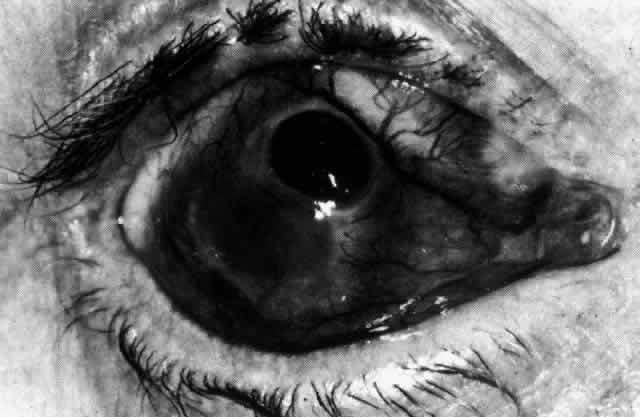

Necrotizing Anterior ScleritisdWithout Adjacent Inflammationd(Scleromalacia Perforans) Necrotizing anterior scleritis without adjacent inflammation appears to be a well-defined condition with little relation in clinical features to necrotizing scleral disease, even though the pathology is similar and the final result is the same. Scleromalacia perforans is characterized by the almost total lack of any symptoms. It occurs almost exclusively in patients with long-standing polyarticular rheumatoid arthritis, the majority of whom are female (Figs. 49 and 50; Color Plate 1E).